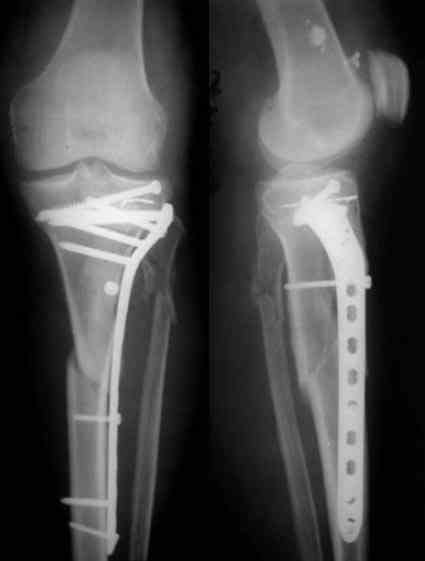

В заключение - клинический пример хирургического лечения похожего перелома из моего архива (1,2). После анатомичной репозиции суставной поверхности с введением стягивающего винта замещён дефект (3,4). Метадиафизарная часть перелома шинирована блокированной пластиной без обнажения отломков (5,6,7).

Большое спасибо! Благодаря Вашим советам я принял решение начать с артротомии, остеосинтеза мыщелков стягивающими винтами. С последующим остеосинтезом пластиной с угловой стабильностью. От артроскопии решил отказаться. Посоветуйте, пожалуйста, какова должна быть длина пластины (кол-во отверстий по диафизу). Это важно, так как пациентка приобретает конструкцию. И большого выбора на операции у меня не будет (максимум 2-3 пластины), поскольку в наличии наких конструкций в клинике нет. Фирма заказывает их в Польше. Мне нужно заказать конкретных 2-3 пластины и винты к ним. На снимке - выбраная мной пластина, но я не уверен насчет длины.